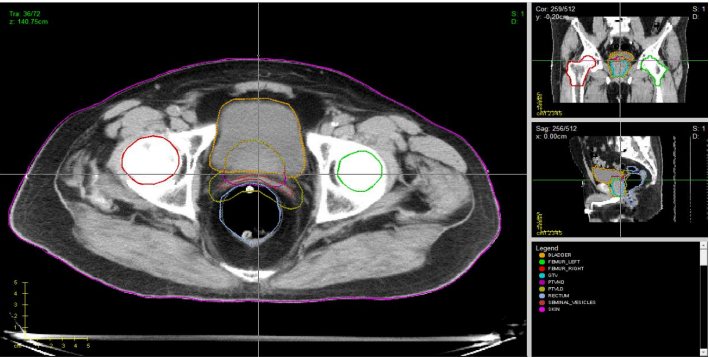

DEVELOPING NUMERICAL METHODS AND SIMULATIONS FOR TRAININGS IN RADIOTHERAPY

Development of simulation and forecasting models and integration with the TCIA database of medical images